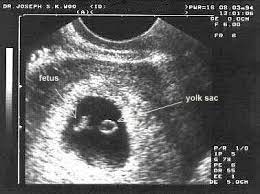

23+ 1 Cm Bebek Kaç Haftalık Görüntüler. Bilinmesi gerekir ki, tıbbi gebelik 4.haftadan. Kaç haftalık hamileyim, bebeğim kaç aylık hesaplama, gabelik haftası ve bebek gelişimi. Adetlerin düzensiz görülmesi, tüp bebek tedavisi ile hamile kalınması, ovülasyon tarihinin gecikmesi, son adetin başlangıç tarihinin yanlış hatırlanması. Anne adaylarının bu 9 aylık yani 40 haftalık bekleyiş süresini sizlere hafta hafta sunmaya çalışacağız. Burada esas alınması gereken takip etme yöntemi hafta hesabı olmalıdır.

Burada esas alınması gereken takip etme yöntemi hafta hesabı olmalıdır. Iri bebeklerin normal doğumu esnasında anne adayında vaginal, perinel yırtılmaları yanında bebeklerin doğması esnasında bazı müdahaleler gerekebileceği belirtilir. Ayrıca bebek ay hesaplama işlemini kolaylaştırmak için yukarıdaki görsele göz atabilirsin. Bebeklerin akciğer gelişimi hızlanmaya başlar. Kaç haftalık hamileyim diye merak ediyorsanız, hesaplama şeklini seçtikten sonra ilgili tarihi giriniz ve hesapla butonuna basınız.